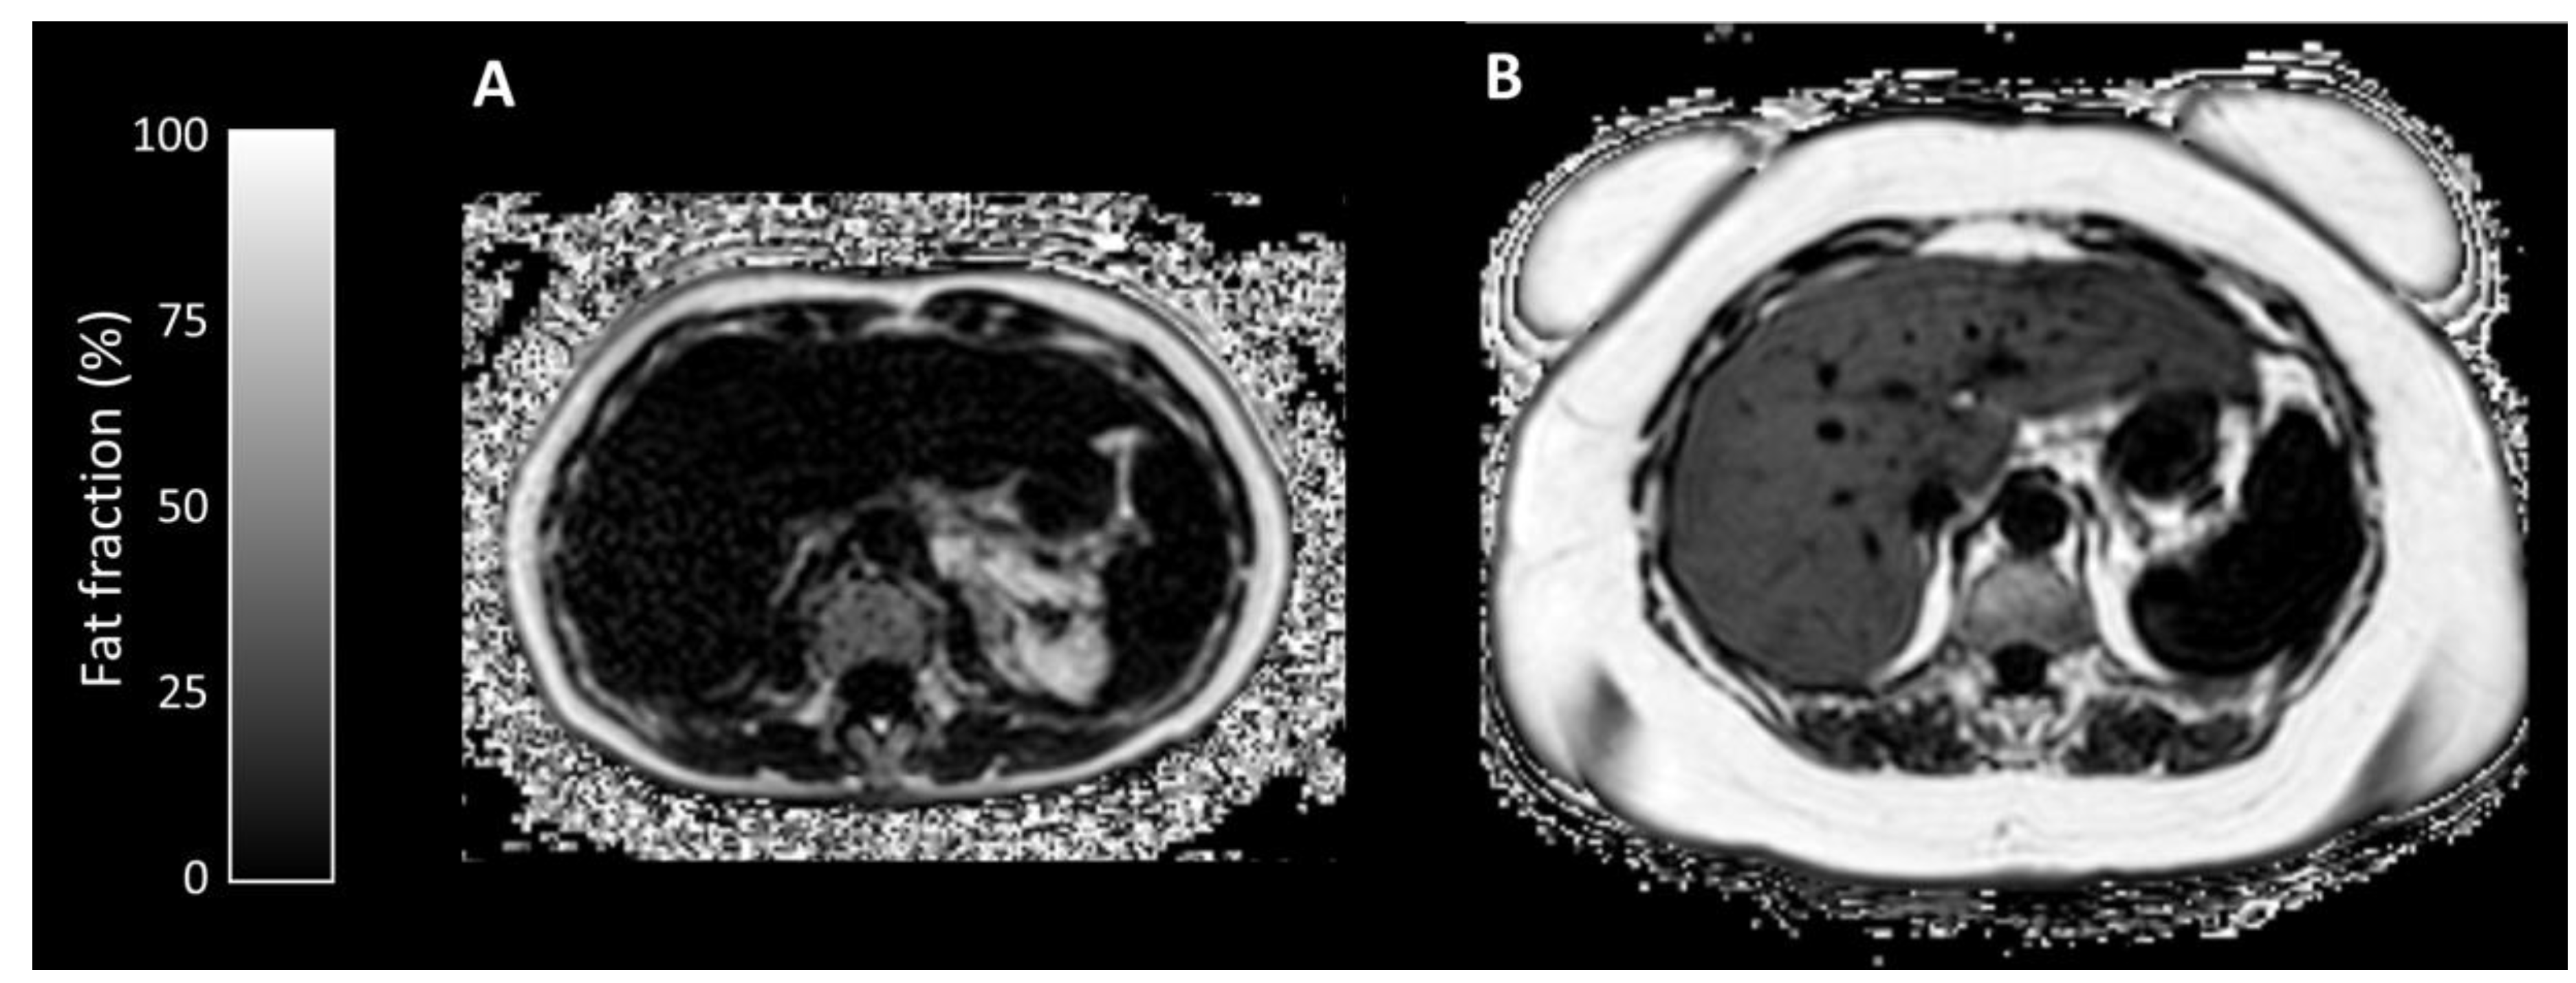

Appendix A.1.2. Proton Density Fat Fraction/T2* Mapping

Appendix A.2.1. Proton Density Fat Fraction/T2* Mapping

| Liver Fat Fraction (%) | 2.14 (1.4–4.2) | 10.90 (2.2–27.4) | 0.032 |